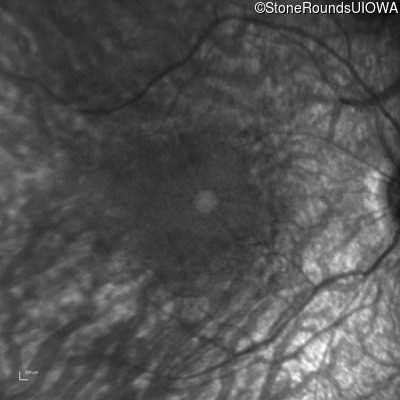

Infrared Fundus Photograph - Right - 20/50

Exemplar

Infrared Fundus Photograph - Right - 20/63